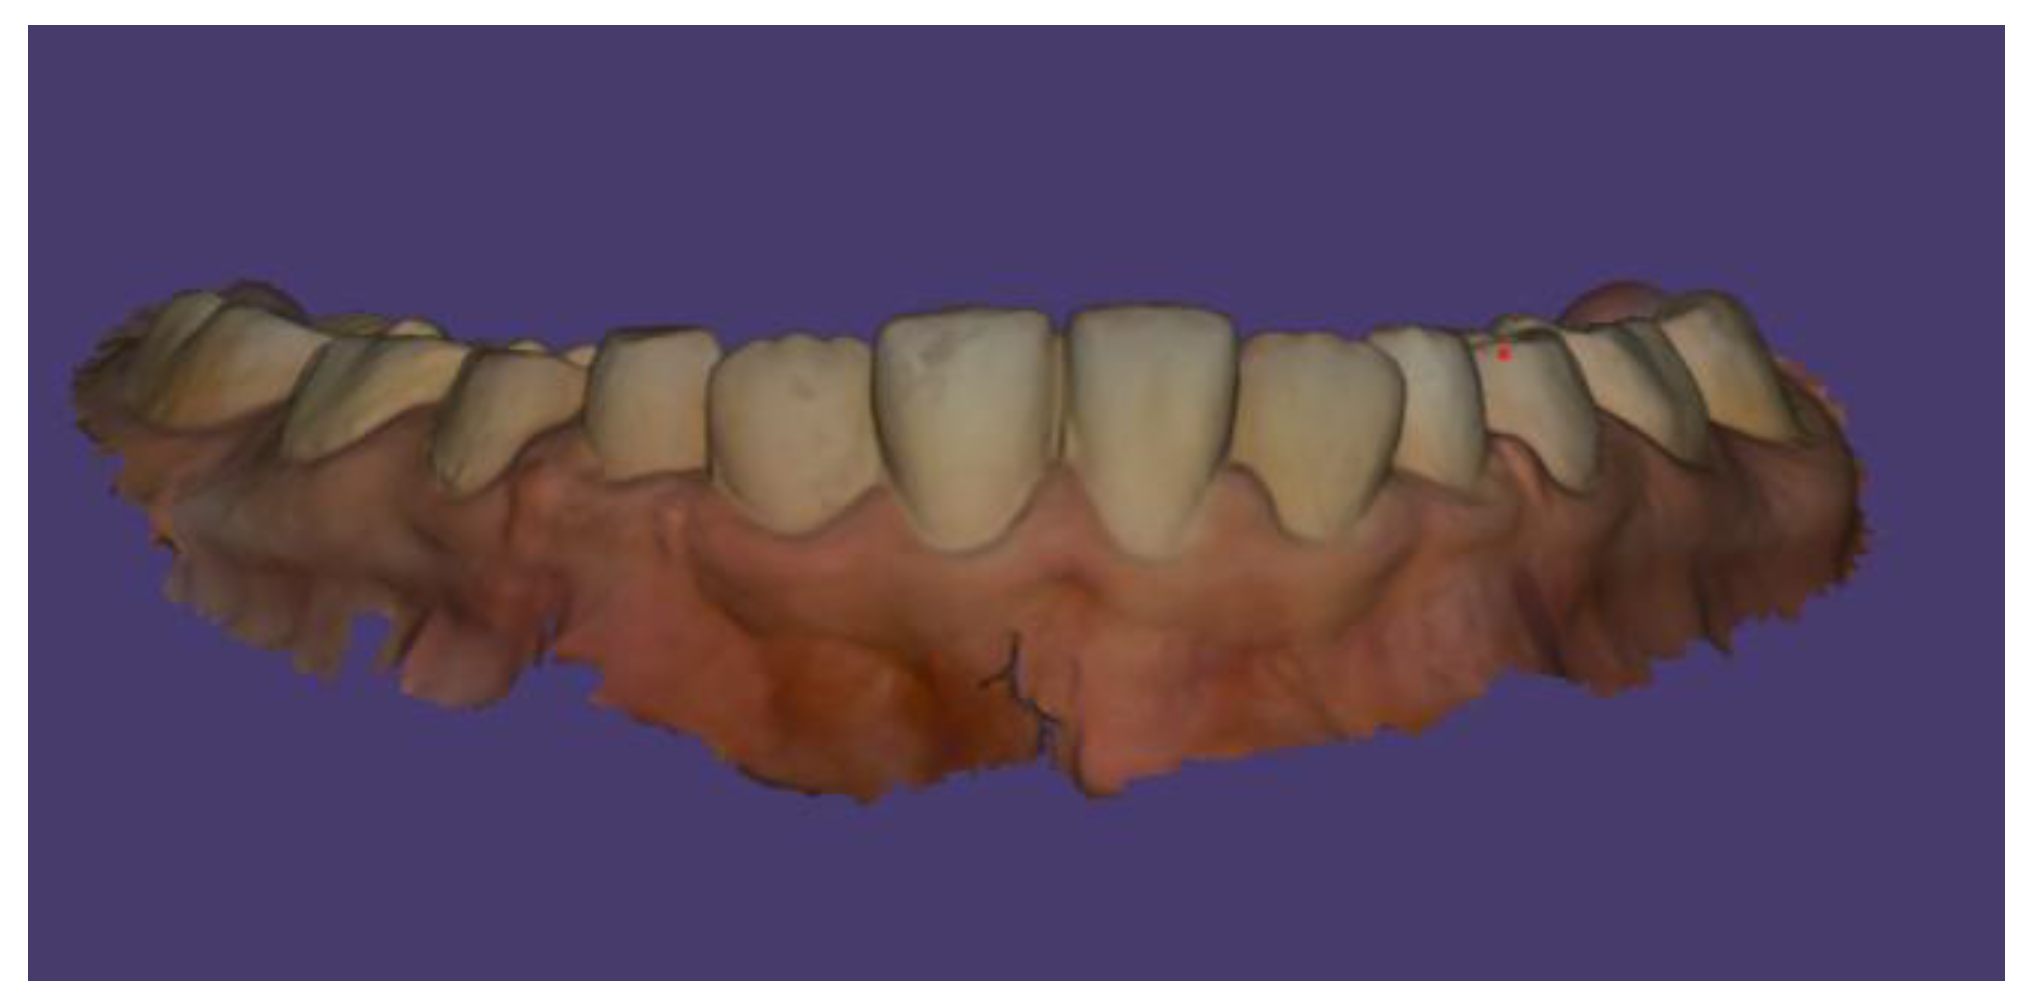

Case Description